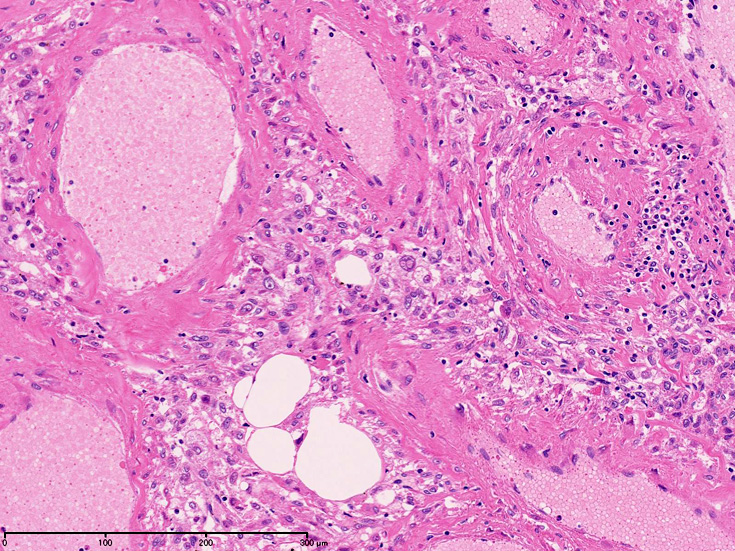

右腎腫瘍組織所見†

組織では血管, 平滑筋, 脂肪組織より構成され, 無秩序に混在する。

- 血管周囲類上皮細胞由来の腫瘍性病変と考えられている。肝のAMLoma, 肺のLAMなどが類似病変*1

- 成熟脂肪組織はしばしばfat necrosis, lipophage, 巨細胞をともなって巨大腫瘤をつくるが, どの成分も主成分になりうる。

- 平滑筋細胞は血管壁外層と密接に関連しており同部位より発生しているように見える。筋細胞は放射状に配列し, 長円形核の長軸は血管に対して直角となるhair-on-end像を示す。

- 平滑筋はしばしば錯綜し束状に腫瘍全体を走行し島状の脂肪組織や血管集簇巣に中断される。糸球体内に腫瘍が増殖することもある。腎外病変も同様の組織所見を示す。

顕微鏡で平滑筋だけにより構成される, 広い部分が認められ、核腫大, hyperchormasia,少数の核分裂像が出現することがある。細胞質内顆粒が見られることがある。

かなり大きな部分で未熟な平滑筋あるいはmyoblast増殖を認めることがある。核は類円形で細胞質は淡明である。細胞は中心の細動脈に対してpalisade構造をとる。

- 血管は特徴的な構成成分でとても厚く異常な壁をもつ。多くの領域で血管の筋組織は厚い線維結合組織で置換され厚みは不規則となりArteriovenous malformationに認められる動脈化静脈に類似する。内弾性板は通常欠損しているか存在しても断片化, 複層化しボロボロである。

- AMLomaの血管は蛇行し壁が部分的にひ薄化拡張して, 小型の静脈瘤様動脈瘤を形成している。